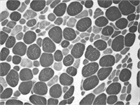

1. ステロイドミオパチーとは、グルココルチコイドによって誘発されるミオパチー(筋疾患)である。